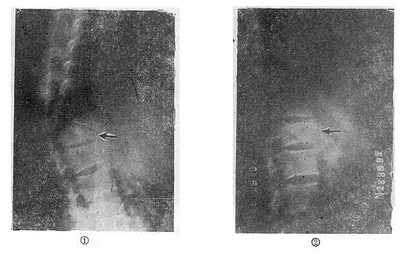

图73-10 攀索叠砖法 (一)单纯楔状压缩骨折的治疗 轻型的压缩骨折,可以采用保守治疗方法。天津医院骨科发掘我国古代医学遗产,创建了“垫枕背伸肌锻炼法”,是一种可行方法(图73-11)。具体做法为病人仰卧硬板床上,腰部用塔形枕垫起,垫枕正对骨折部位,保持脊柱过伸位。先静卧2~3天,待骨折处出血停止,疼痛减轻及腹气胀反应消退后即开始如图示方法,逐渐加强锻炼。病人卧床3个月,天天坚持锻炼,大部分病人可获得良好的结果(图73-12)。此法的缺点是需较长时间的卧床,且对一些比较严重的压缩骨折,有时复位不够满意。我们经验认为,对于椎体前方压缩50%以上者,特别是青年患者,最好用两根Harrington棍进行手术或Dick法复位固定。可以使骨折解剖复位,而且术后两周即可带石膏围腰或支具下地活动。

图73-12 垫枕背伸锻炼获良好结果 ①骨折初时;②背伸锻炼3个月后 (二)旋转型脊柱骨折的治疗 用Harrington棍法,不能矫正旋转,最好用Luque棍或Dick法进行矫正与固定。两根“L”型金属棍,放在棘突基底两侧,用每一个椎板下穿过的Luque钢丝固定到骨折部位上、下方各三个椎体椎板上,通过弯好弧度的Luque棍的杠杆作用和拧紧Luque钢丝所产生的矫正力,可以矫正旋畸形,并牢固固定骨折。如不合并神经系统症状,1周后即可下地活动。 (三)爆裂型骨折的治疗 如不合并严重的神经系统症状,损伤又在两周以内者,可以用双Harrington法,撑开矫正,或用Dick手术;可以获得满意的结果(图73-13)。复位后需融合相邻两个椎间隙,因为CT常显示在爆裂型骨折中,相邻的上、下两个椎间盘均有损伤,如不融合,日后取棍后会出现腰痛。使用本法时,如前纵韧带完整,则很容易恢复椎体前方的高度。但爆裂型骨折存在下述三种情况时,需行前路减压术:①合并神经系统症状较重者;②就诊较晚,已两周以上者(常常10天以上就复位比较困难);③脊柱CT扫描显示已有较大的骨折片突出椎管内,使髓腔管变窄超过30%以上者,预示后纵韧带已有明显损伤,使用后路手术方法已无法使骨折片复位。Kostuik复习了日本和多伦多治疗脊柱骨折的结果后证实,前路减压术能使膀胱、肛门及肢体功能得到更好的恢复。